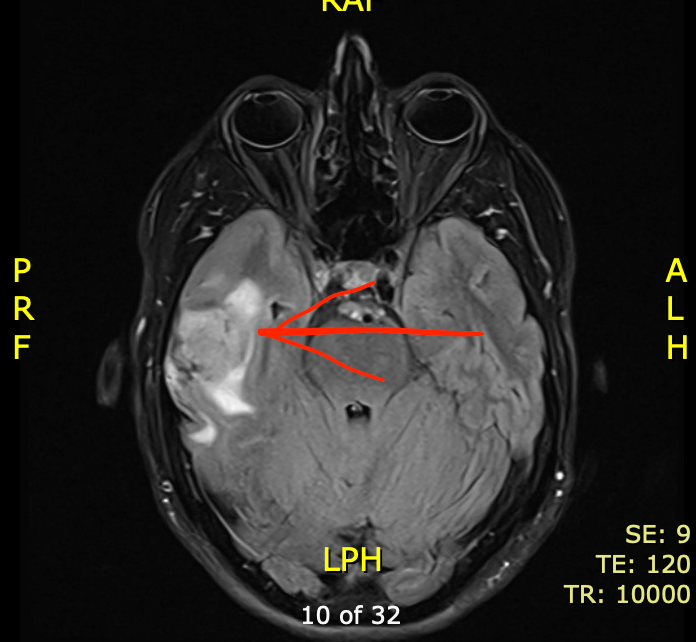

When we arrived in Lima, the doctors discovered a mass in my brain that was causing swelling, which they determined lead to a seizure. I was admitted to the hospital, and further tests showed that I was in immediate danger, so a few days later I underwent brain surgery to remove the mass.